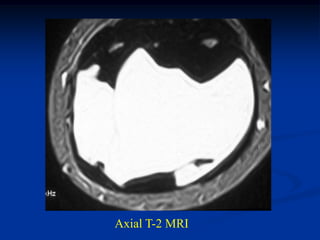

Case #1199

30 year male with

myxoid liposarcoma

posterior thigh

Sagittal T-2 MRI

Case #1199 30 yearmale with myxoid liposarcoma posterior thigh Sagittal T-1 MRI